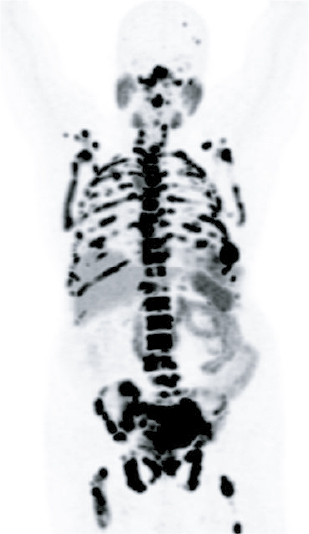

Precision imaging using advanced modalities such as PSMA PET-CT

Accurate identification of disease spread

Radiological Improvement

Resolution of lung metastases

No active lymph node involvement

Significant reduction in bone lesions